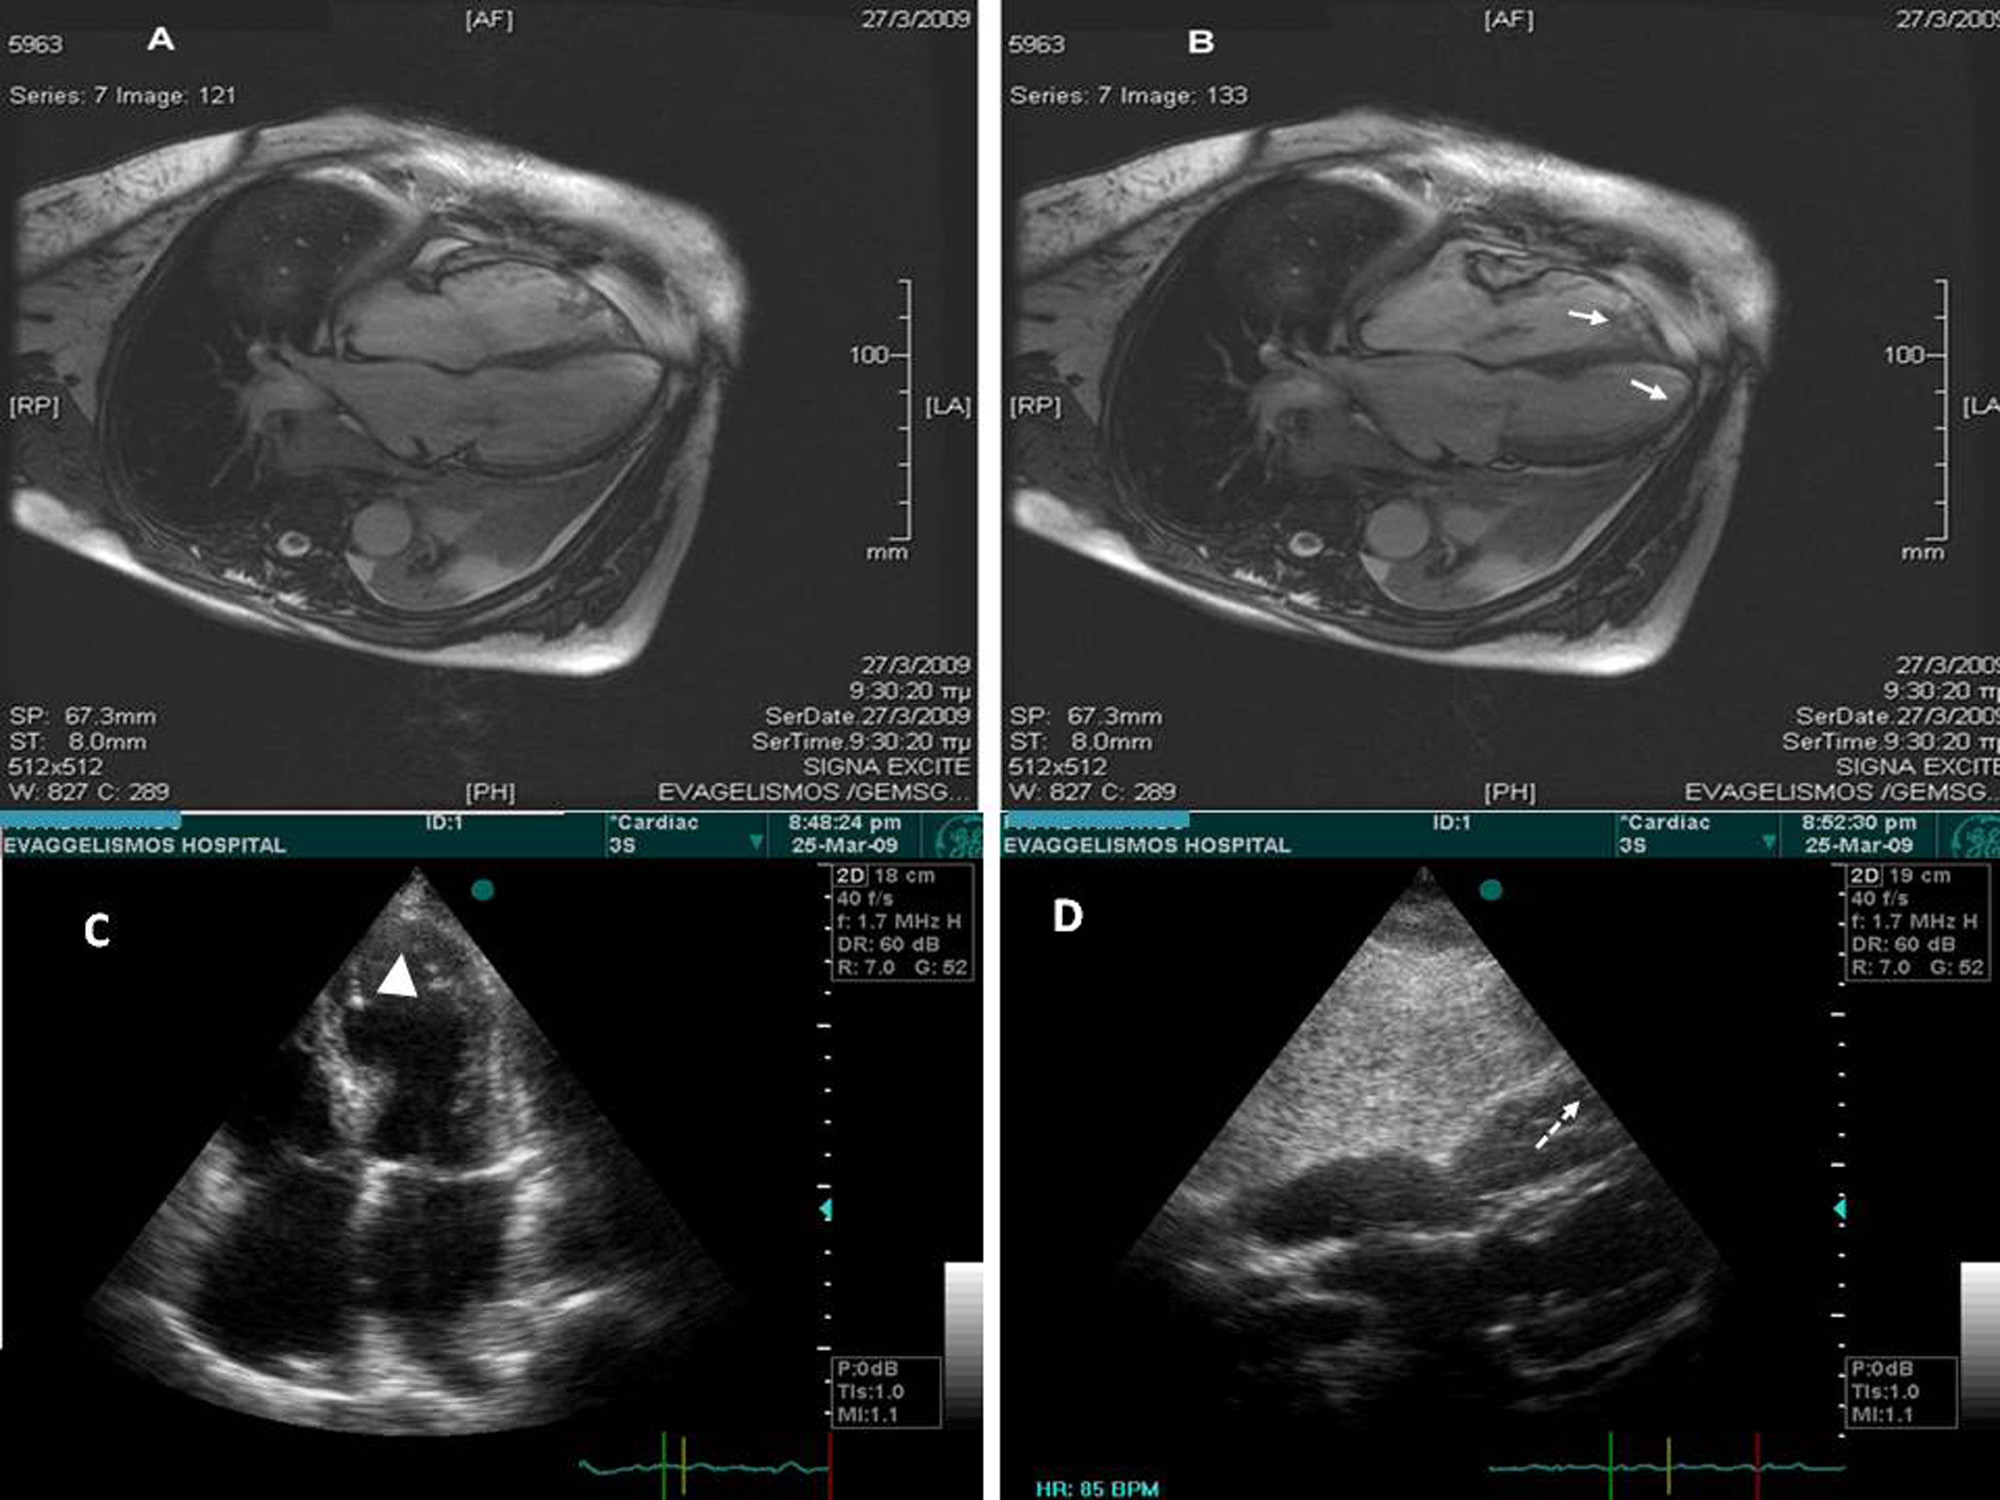

A 68–year–old woman, 4 hours after bronchoscopy, developed symptoms and ECG signs of inferolateral acute myocardial infarction. Emergency coronary angiography showed normal coronary arteries, but LV angiography revealed apical ballooning with apical akinesis diagnostic of Tako-tsubo cardiomyopathy. One day later cardiac MRI additionally disclosed right ventricular apical involvement, which has been reported in only very few cases in the literature associated with worse prognosis. Fortunately, our patient had an uneventful course and complete recovery.Downloads